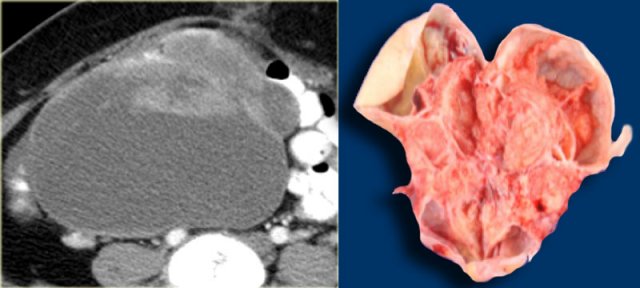

Ultrasound shows a very large multi-loculated cystic lesion in the region of the right adnex.

Some locules are anechoic. Others contain uniform low-level echoes, consistent with proteineous content, such as hemorrhage or, in this case, mucin. The septations are thin, except for the dorsal septations that appear somewhat thicker, partially caused by the lower scanresolution at great depth. The septations are avascular. There are no solid components. There was no ascites.

Despite the absence of solid components and despite the absence of vascularity on color Doppler, the size and the multi-loculated aspect of this lesion are suspicious for a cystic neoplasm and warant further evaluation.

The CECT shows similar findings. The locules are of different attenuation, consistent with varying protein content.

There is no ascites orperitoneal deposits and no lymphadenopathy.

At pathology this was a mucinous cystadenocarcinoma of low malignant potential.

Specimen of the mucinous cystadenocarcinoma Specimen of the mucinous cystadenocarcinoma

The thin, relatively avascular septae, the absence of frank solid components, the absence of ascites and peritoneal carcinomatosis and the absence of invasion, suggest a lesion of low malignant potential (LMP).

Note however, that this diagnosis can not be made on imaging findings alone.

Especially the absence of invasion in ovarian stroma cannot be judged reliably on imaging.